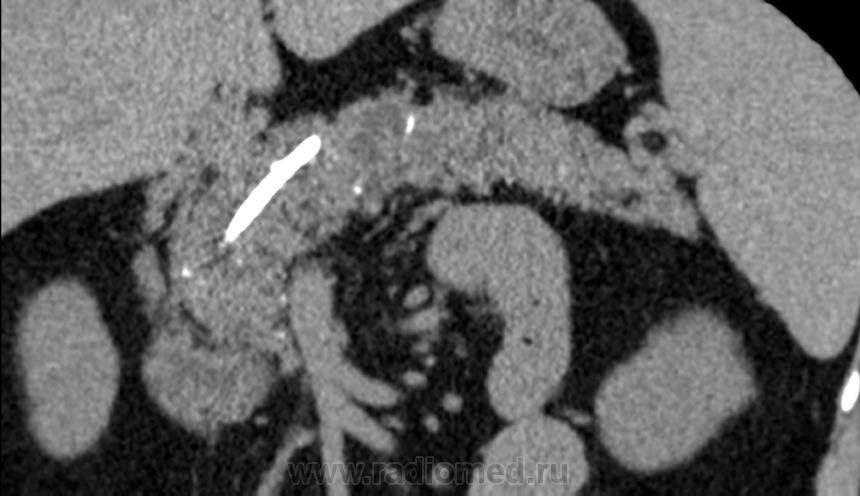

Итак пациент мужчина 34 года, в анамнезе - 16 эпизодов острого панкреатита (!). Пациенту была выполнена ЭРХПГ которая выявила наличие двух стриктур протока Вирсунга в области головки поджелудочной железы (доброкачественная стриктура Вирсунгова протока). На представленных мной изображениях определяется неоднородная структура поджелудочной железы с гиподенсными участками в области тела/хвоста и наличием паренхиматозных кальцификатов (b & c). Такая картина указывает на хронический панкреатит. В области головки визуализируется стент (a), установленный в Вирсунгов проток, с свободным концом в просвете 12-ти перстной кишки. Такое стояние стента является правильным. На данный момент, единственной адекватной терапией при доброкачественных стриктурах протока поджелудочной железы (и при некоторых опухолях исходящим из протока или обтурирующих его, когда невозможно выполнить резекцию) является эндоскопическое стентирование протока, что обеспечивает нормальный отток секрета поджелудочной в кишечник.